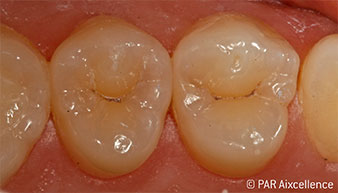

Рис. 1. Начальный вид зубов без клинических признаков кариеса

Рис. 2. Освещение зондом Facelight используется здесь в качестве трансиллюминации для распознавания непрозрачных областей. Соединения порфирина при такой форме освещения не активируются